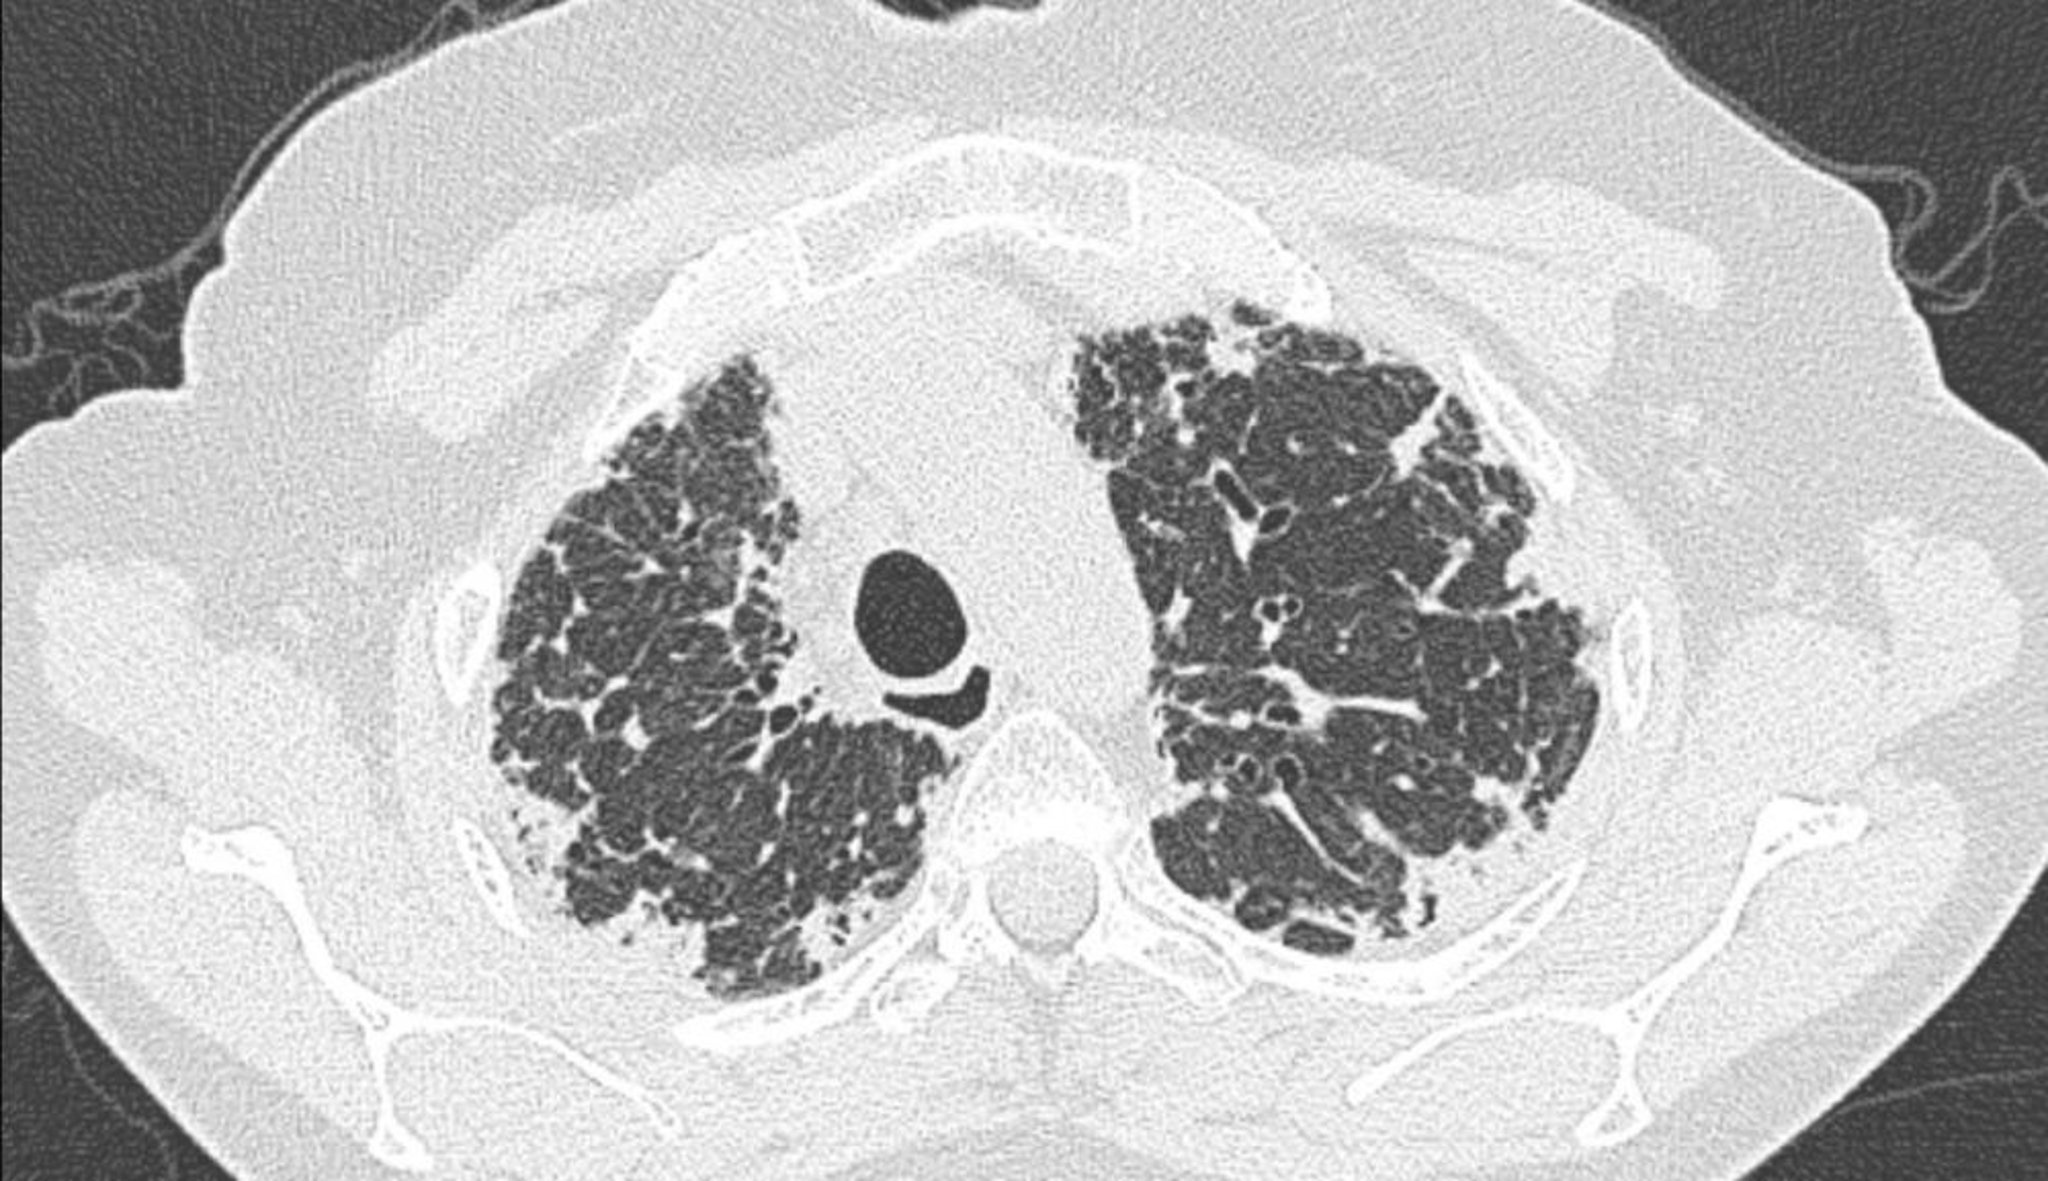

Fibroelastose pleuroparenquimatosa idiopática

TC do tórax mostra espessamento pleural e subpleural.

Imagem cedida por cortesia de Joyce S. Lee, MD, MAS.